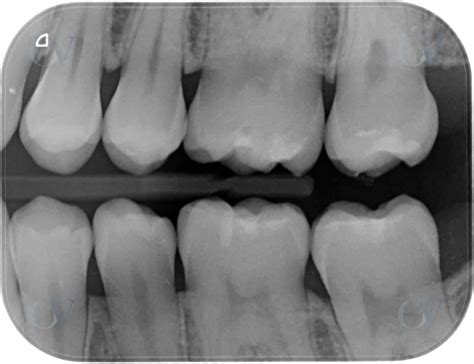

La prueba diagnóstica más adecuada para las caries interproximales será una radiografía oral y una exhaustiva exploración dental. Para poder asegurarnos de que el paciente sufre de caries interproximales, el odontólogo le realizará una radiografía oral y una exploración dental. De está manera, podrá detectar las caries interdentales a tiempo y tratarlas.

Sin embargo, es importante tener en cuenta que las radiografías de aleta de mordida a menudo no pueden detectar las lesiones iniciales del esmalte, por lo que hasta que las lesiones no han penetrado en la dentina no se pueden diagnosticar. Otro problema asociado con este tipo de radiografías de aleta de mordida es que una radiolucidez proximal no siempre refleja la presencia de caries; esa radiolucidez puede deberse a un desgaste a nivel del cuello, producida por la disminución de la atenuación de los rayos X en el cemento del diente.